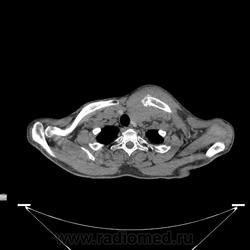

Миелома (плазмоцитома).

Недавний случай. Подтвержден гистологически.  По сцинтиграфии дополнительные очаги гиперфиксации РФП с некоторых ребрах и крестцово-подвздошных сочленениях.